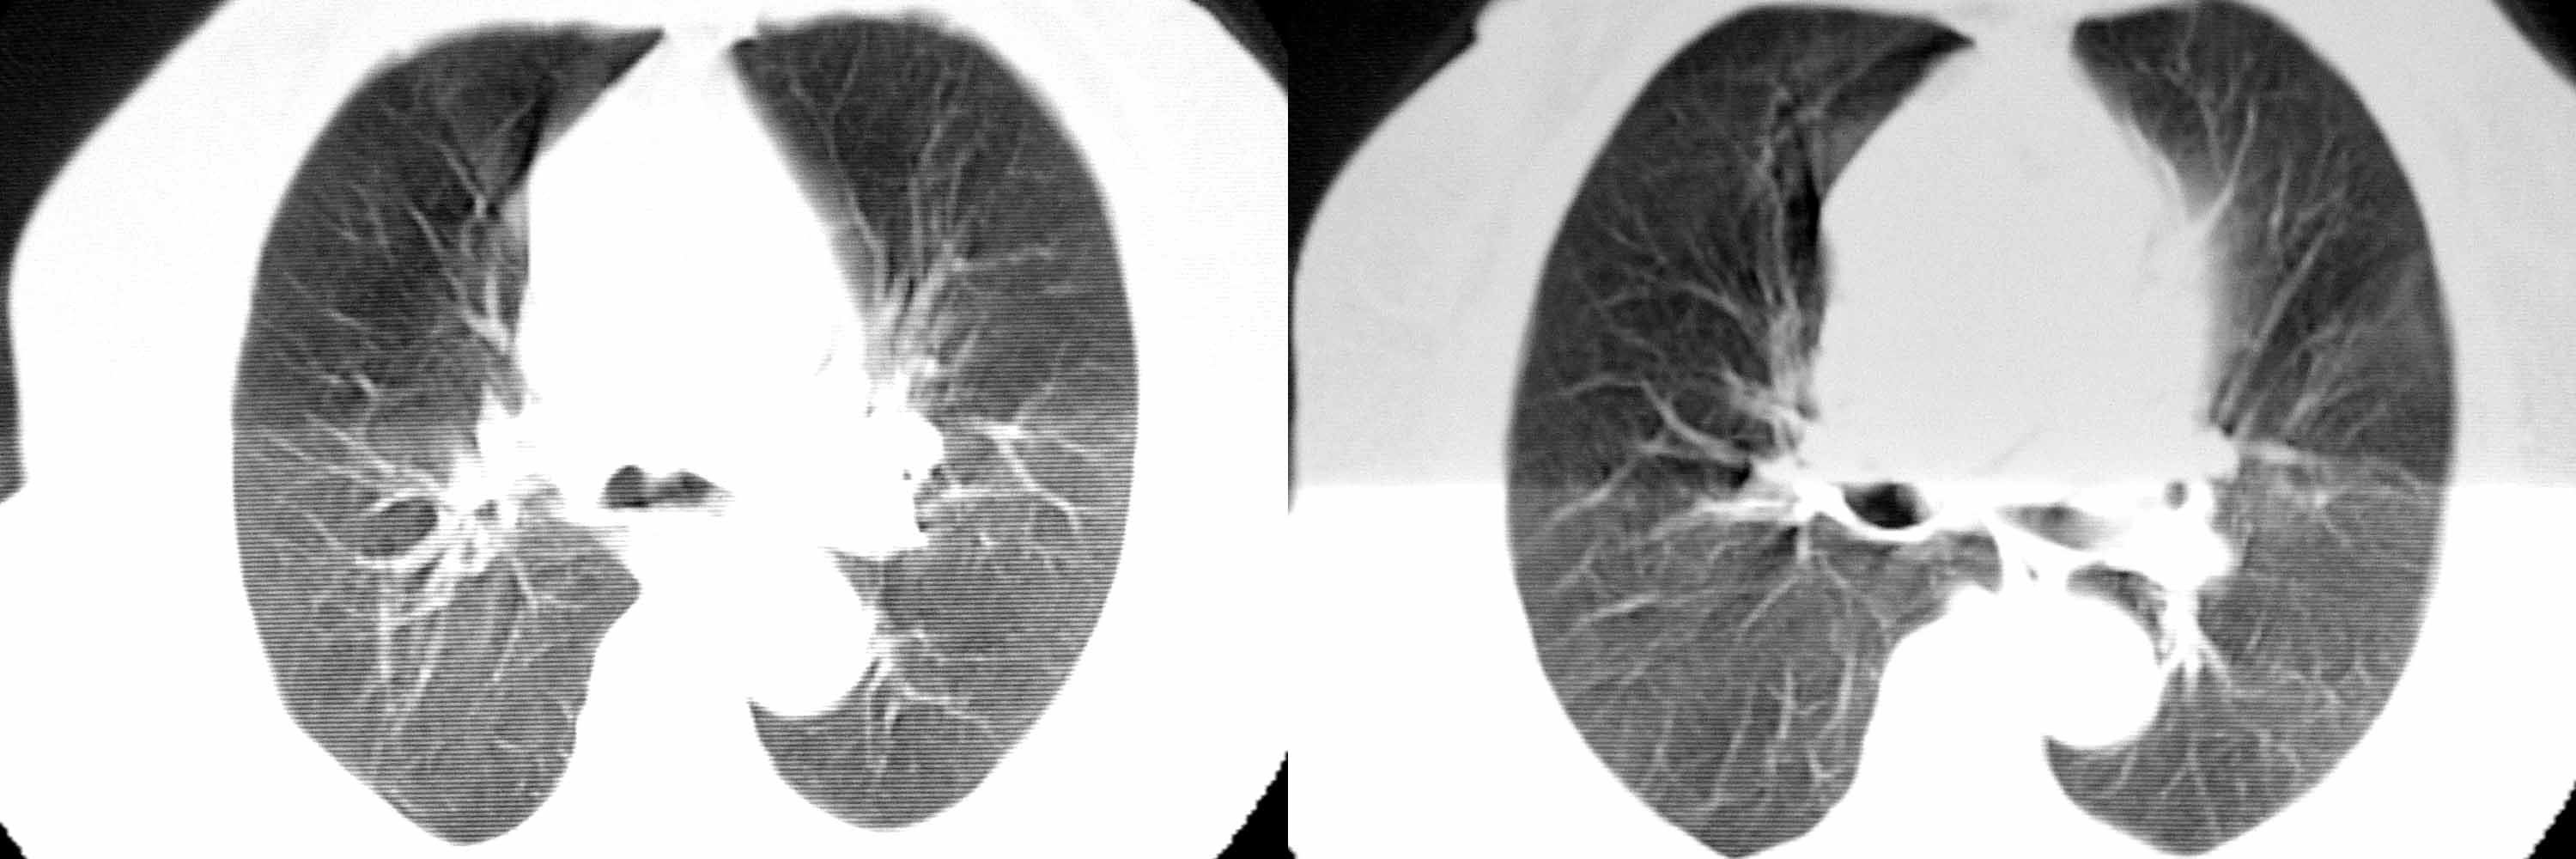

女78岁咳嗽咳痰无咳血平片报右上肺不张、慢支、肺气肿、请老师们帮忙看看,箭头所指是什么?是占位吗?有肺气肿吗?谢谢

箭头所指考虑血管影;纵隔内及双肺门区多发淋巴结钙化;不支持肺气肿。

箭头所指考虑血管影(头臂血管);纵隔内及双肺门区多发淋巴结钙化;不支持肺气肿。